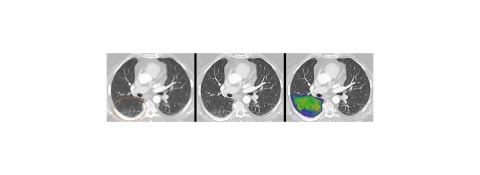

Mit einem neuartigen Systemkonzept und neuer Detektortechnologie läutet dieses System eine neue Ära in der Computertomographie ein, einer Technologie, die die Richtung vieler medizinischer Entscheidungen beeinflusst. Dank der Bilder quantenzählender CTs profitieren weltweit mehr Menschen von präzisen und umfassenderen Untersuchungen bei niedriger Strahlen- und Kontrastmitteldosis – von onkologischen Verfahren über Herzdiagnostik bis hin zu Verlaufskontrollen der Lunge bei Atemwegserkrankungen.

Der von Siemens Healthineers entwickelte quantenzählende CT-Detektor wandelt die Röntgenstrahlen nicht mehr in sichtbares Licht um. Die Röntgenphotonen werden direkt in vollständig digitale elektrische Signale umgewandelt und dann ohne Informationsverlust gezählt. Dies bietet eine Fülle völlig neuer, klinisch relevanter Informationen und verbessert die Bildschärfe sowie den Kontrast.